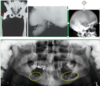

What is this radiographical finding?

Metastatic Carcinoma to Jaw Bones

C. Periapical image of a metastatic lesion of breast carcinoma; note the irregular widening of the periodontal membrane spaces and patchy sclerotic bone reaction, especially around the roots of the molars